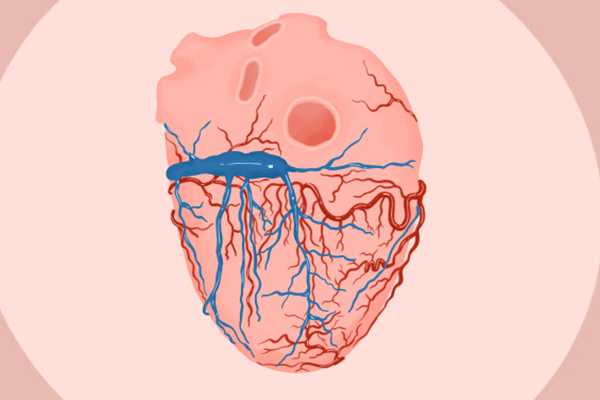

2、健康心脏。卵磷脂可以调节人体中胆固醇的含量,降低胆固醇、高血脂、冠状粥脉硬化性心脏病的发病率,让心脏更健康。

3、保护血管。卵磷脂可以乳化和分解油脂,还可以促进血液循环,清除血液中的过氧化物和多余胆固醇、脂肪,减少脂肪在血管壁的停留,防止血管内膜损伤,让血管更加健康干净,从而预防和治疗高血脂、高胆固醇以及动脉硬化。